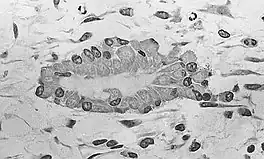

At this stage of development, changes in the morphology of the osteoprogenitor cells occur: Their shape becomes more columnar and the amount of Golgi apparatus and rough endoplasmic reticulum increases. Eventually, all of the cells within the nidus develop into, and display the morphologic characteristics of, an osteoblast. Then the osteoblasts create an extracellular matrix containing Type-I collagen fibrils, which is osteoid. The osteoblasts, while lining the periphery of the nidus, continue to form osteoid in the center of the nidus. Some of the osteoblasts become incorporated within the osteoid to become osteocytes.[1]

At this point, the osteoid becomes mineralized resulting in a nidus consisting of mineralized osteoid that contains osteocytes and is lined by active osteoblasts. The nidus, that began as a diffuse collection of MSCs, has developed into woven bone, the most rudimentary bone tissue.[1]